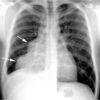

1. U trung thất trước

– Tạo góc tù với trung thất.

– Đè đẩy đường trung thất trước.

– Xóa mờ khoảng sáng sau xương ức.

– Xóa mờ góc tâm hoành.

– Xóa bờ, đè đẩy động mạch chủ lên.

– Dấu hiệu che phủ rốn phổi2. Đặc điểm u quái

– Các tổn thương lành tính thường có hình tròn, bầu dục, bờ nhẵn.

– Các u quái trưởng thành, ngấm vôi rất đậm dạng xương hoặc răng trong tổn thương. Các cấu trúc mỡ có thể biểu hiện vùng sáng hoặc có thể gặp hình ảnh mức dịch-mỡ trong tổn thương.

– Dấu hiệu ác tính: xâm lấn xung quanh: thành ngực, dịch màng phổi, dịch màng tim, di cănIV. Chẩn đoán CLVT